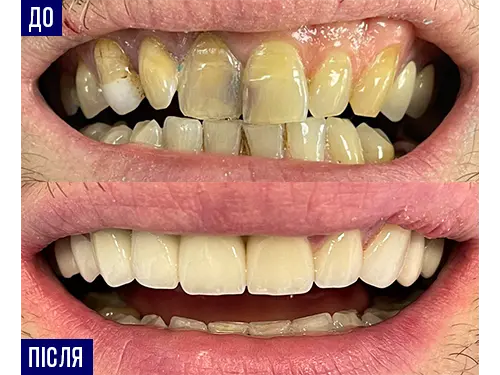

Наші роботи